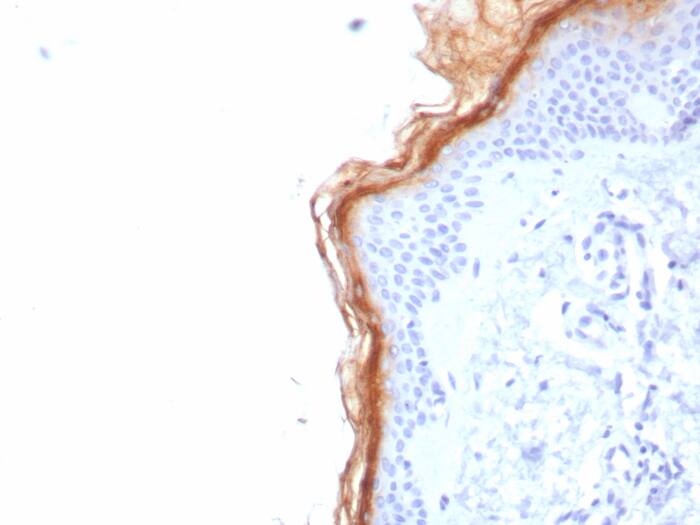

Immunohistochemistry-Paraffin: S100G Antibody (S100G/7517) [NBP3-23875] -

Formalin-fixed, paraffin-embedded human skin stained with S100G antibody (S100G/7517). HIER: Tris/EDTA, pH9.0, 45min. Secondary: HRP-polymer, 30min. DAB, 5min.